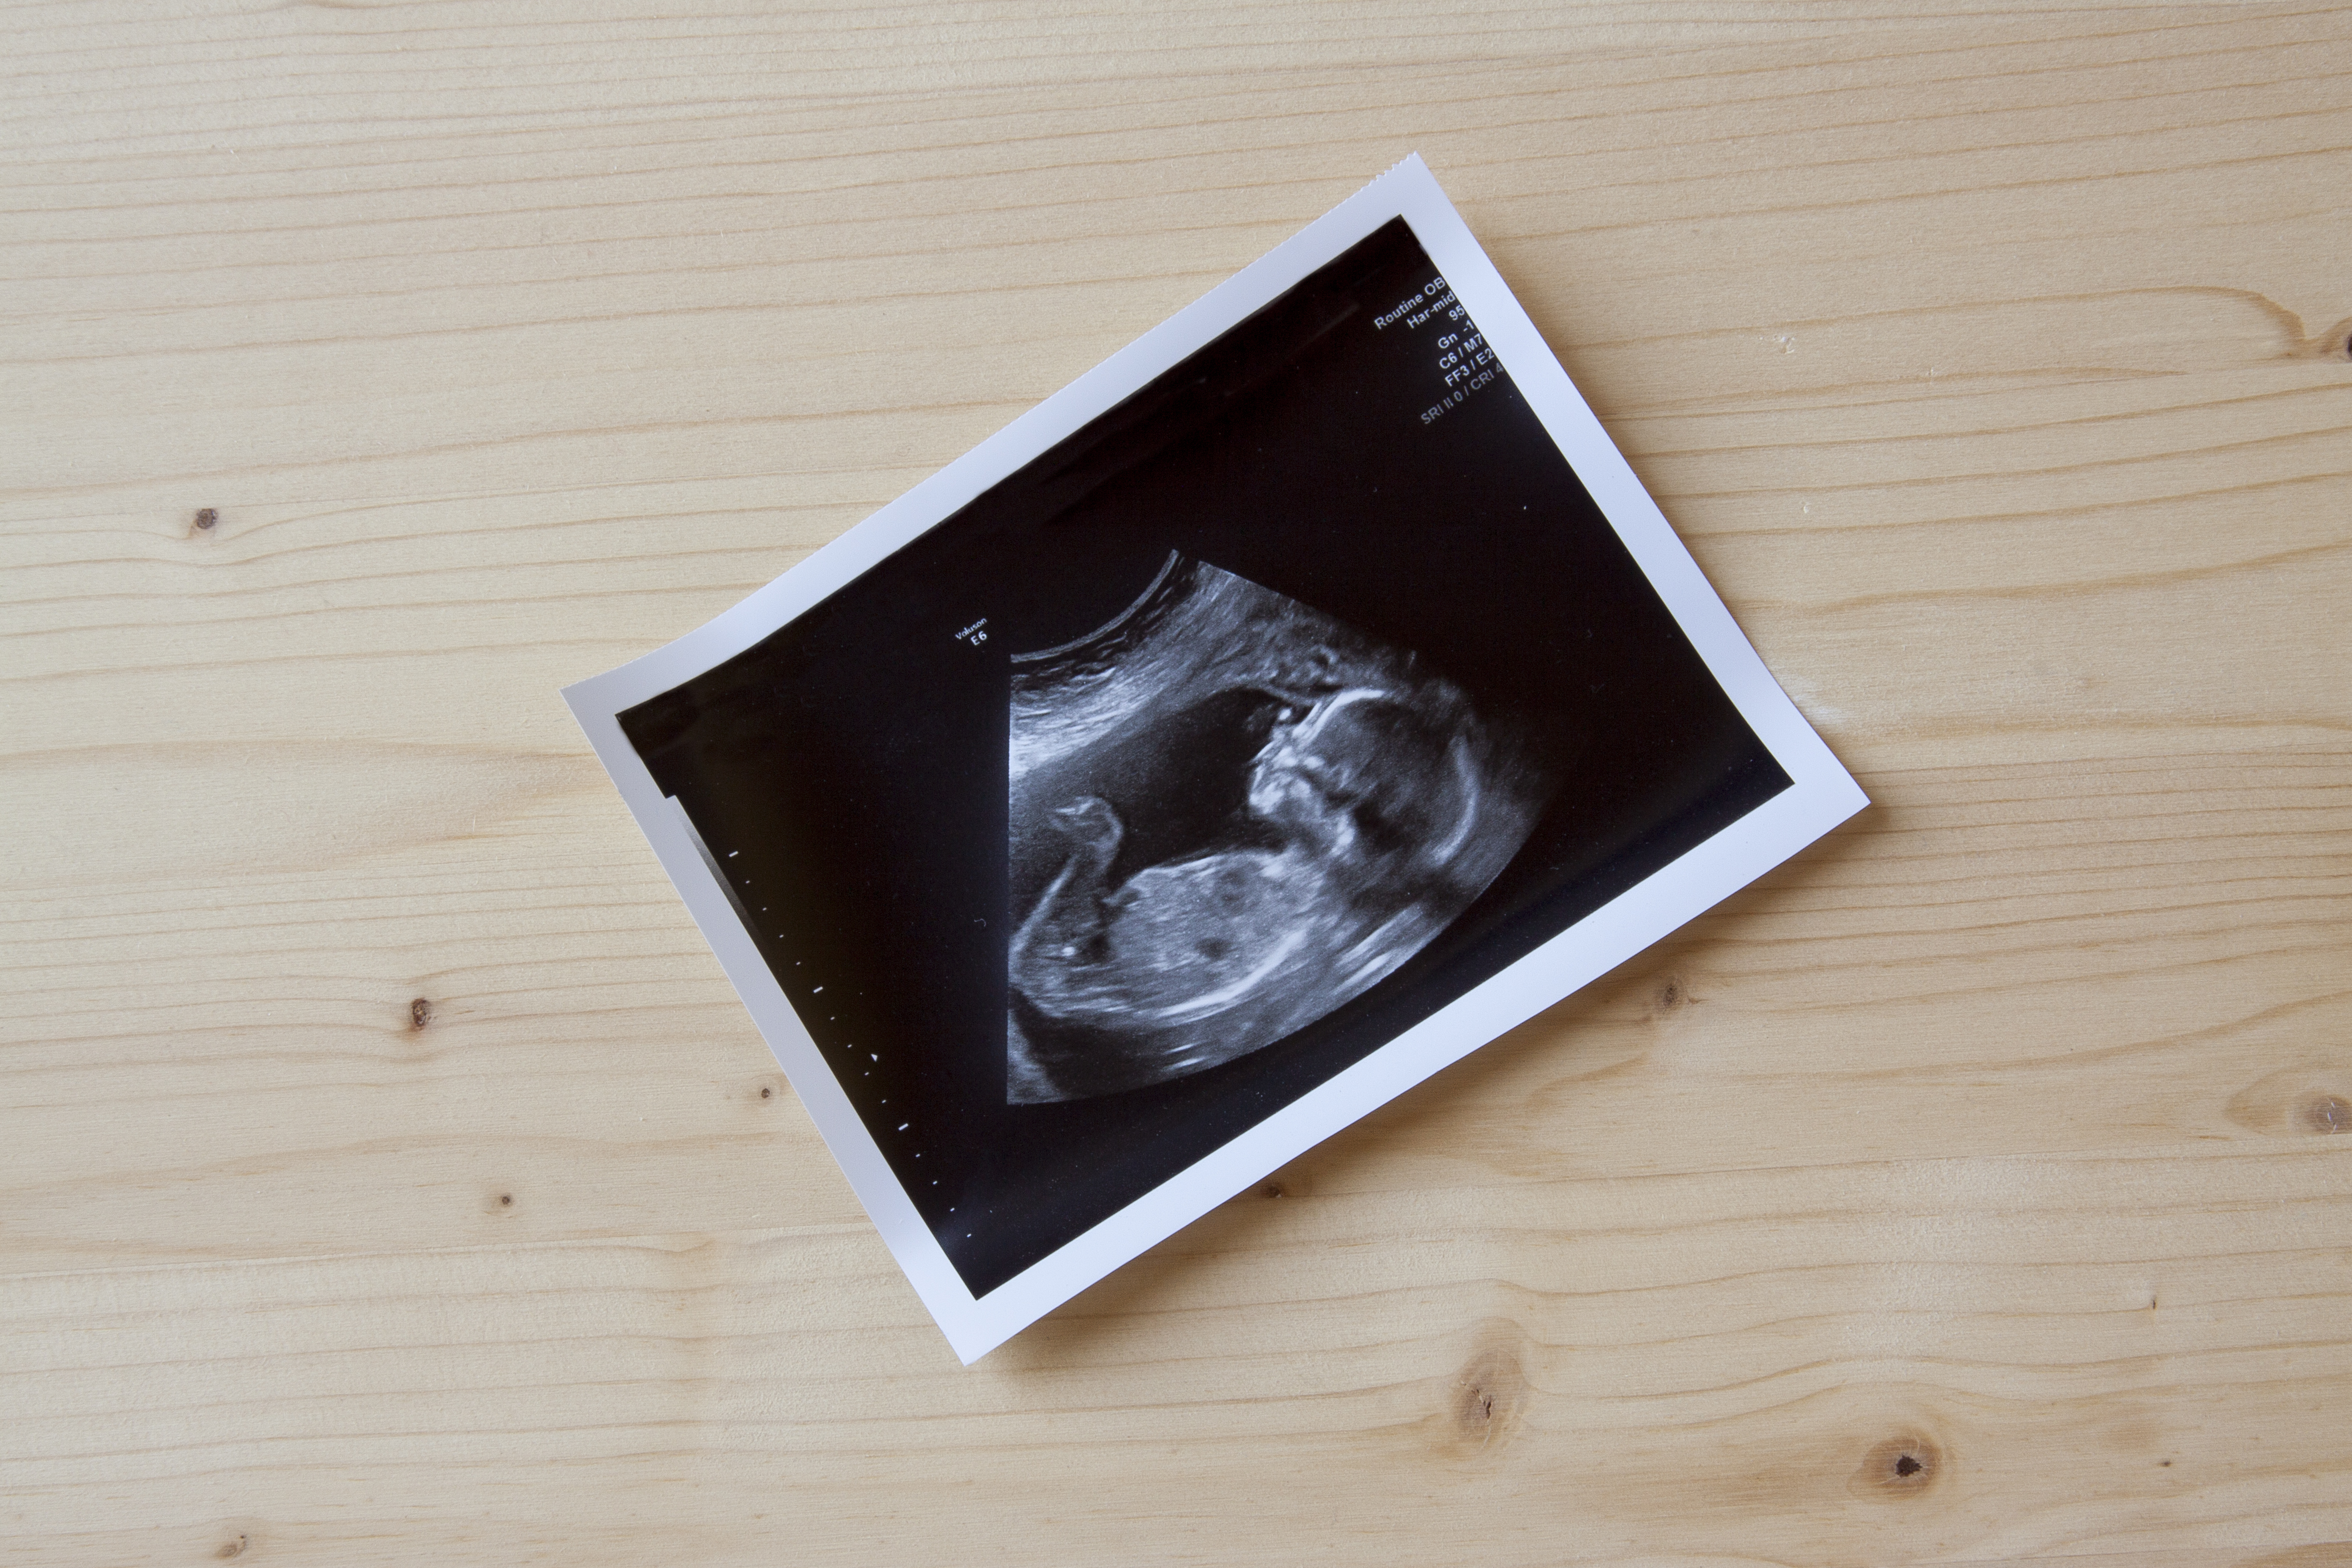

Development of the foetus

By now, the foetus is usually between 6 and 7 cm long and weighs around 40 grams, but this can vary from pregnancy to pregnancy. In early pregnancy, amniotic fluid is mainly produced from the mother's blood. Urine production starts as the foetus develops. The amniotic fluid then becomes a mixture of fluids from both the mother and the foetus. The amount of amniotic fluid gradually increases, providing the foetus with more space to move around freely.

During this period, the nails on the fingers and toes develop and the bones begin to harden.

By the time of transition to the second trimester, the placenta is fully developed. From now on, the placenta will transfer nutrients and oxygen to the foetus.